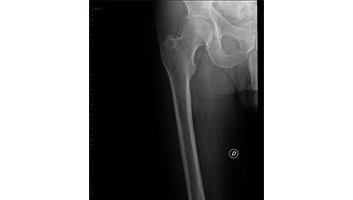

- Rx des os et des articulations